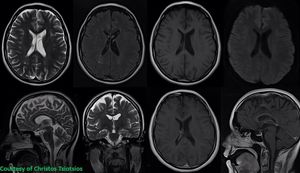

For certain patients that undergo magnetic resonance (MR) examinations, the experience may be associated with emotional distress. In these cases, we need to use rapid imaging protocols. Figure shows a fast protocol for the imaging of the brain in a sedated patient with claustrophobia. Upper row (from left to right): T2-w ax, T2-w FLAIR ax, T1-w ax, DWI (b1000). Bottom row (from left to right): T2-w sag, T2-w cor, T1-w ax (post Gd), T1-w sag (post Gd). Total imaging time less than 14 minutes for 9 sequences (T1-w cor post-Gd is not shown). Images courtesy of @tsiochris